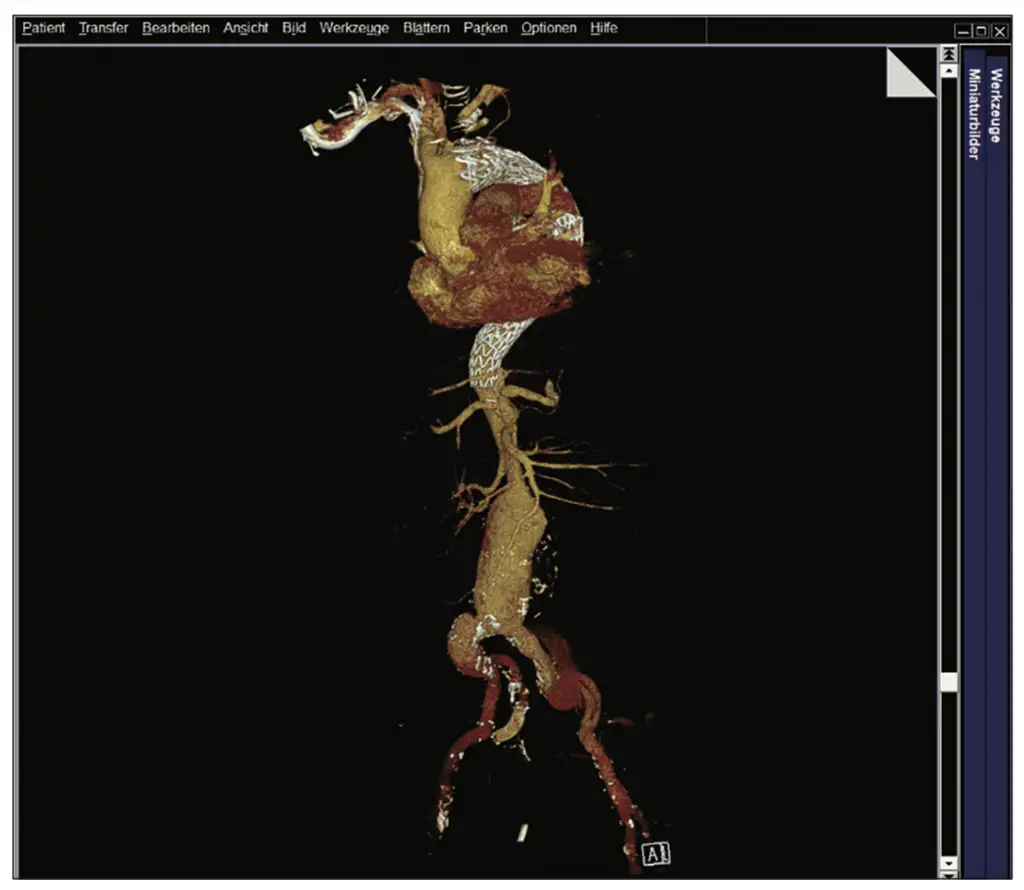

Im Herbst 2023 wurde bei dem damals 62-jährigen Mann als Zufallsbefund im Rahmen einer urologisch veranlassten CT-Untersuchung eine komplexe thorakoabdominelle Aortendissektion Typ Standford B diagnostiziert. Distal setzte sich die Dissektion in ein mutmaßlich vorbestehendes infrarenales Aortenaneurysma fort und bildete ein Aneurysma dissecans von 8 cm Durchmesser. Die Dissektion endete in der linken A. iliaca externa. Zudem bestanden Aneurysmata der A. iliaca externa. Das wahre Lumen war schmächtig im Sinne eines subtotalen True-Lumen-Kollaps.

In interdisziplinären Fallkonferenzen wurden die möglichen Versorgungsoptionen diskutiert und schließlich fiel unter Einbeziehung des Patienten die Entscheidung zu einer dreizeitigen endovaskulären Versorgung. Zunächst erfolgte eine Versorgung der thorakalen Aorta mittels Stentgrafts, die proximale Landezone musste dabei nach vorherigem Debranching mittels Carotido-Carotido-Subclavia-Bypass bis in die Zone 1 nach Ishimaru ausgeweitet werden. Distal erfolgte eine Versorgung der Dissektion der Beckenarterien mit Ausschaltung der Iliacalaneurysmata durch eine beidseitige Implantation eines Iliac-Side-Branch-Devices (Abb. 1 a–c).

Im Dezember 2023 war die abschließende Versorgung mittels individuell angefertigtem thorakoabdominellen Multibranch-Aortenstent mit Landezone in den zuvor implantierten Stents suprarenal bzw. iliacal beidseits geplant. Anatomisch waren zu diesem Zeitpunkt verschiedene Aspekte bekannt und wurden in die OP-Planung, auch zeitlich, miteingeschlossen.

Aufgrund des schmächtigen wahren Lumens sollten Truncus coeliacus, A. mesenterica superior und rechte Nierenarterie mittels Inner-Branches (Custom Design der Firma Jotec/Artivion) erhalten werden. Die linke Nierenarterie wurde explizit nicht miteingeschlossen, da von einem initial funktionslosen Organ ausgegangen wurde.

Als anatomische Normvariante zeigte sich in der Bildgebung ein isolierter Abgang der A. hepatica sin. aus der Aorta entspringend. Geplant war, diesen mit einem Twin-Branch (A. hepatica sin./Truncus coeliacus) zu erhalten. Leider kam es nach der Implantation in den Truncus coeliacus zu einer Kompression und damit zu einem Verschluss der A. hepatica sin. Der entsprechende Anteil des Twin-Branches wurde mittels Vascular-Plug verschlossen.

Trotz dieser positiven Befunde wurde ein langer intensivstationärer Aufenthalt notwendig, da es postoperative Komplikationen wie ein akutes Nierenversagen, eine Pneumonie und ein Delir gab. Allerdings entwickelte sich der Gesamtverlauf schließlich positiv und der Patient konnte über die Reha in die Häuslichkeit entlassen werden. Bildgebend waren die Aneurysmata (abgesehen von einem kleinen Typ 2 Endoleak) ausgeschaltet und die Dissektion regelhaft angelegt. Die Stentgrafts waren einschließlich der viszeralen und iliacalen Branches regelhaft perfundiert (Abb. 5 a und b).